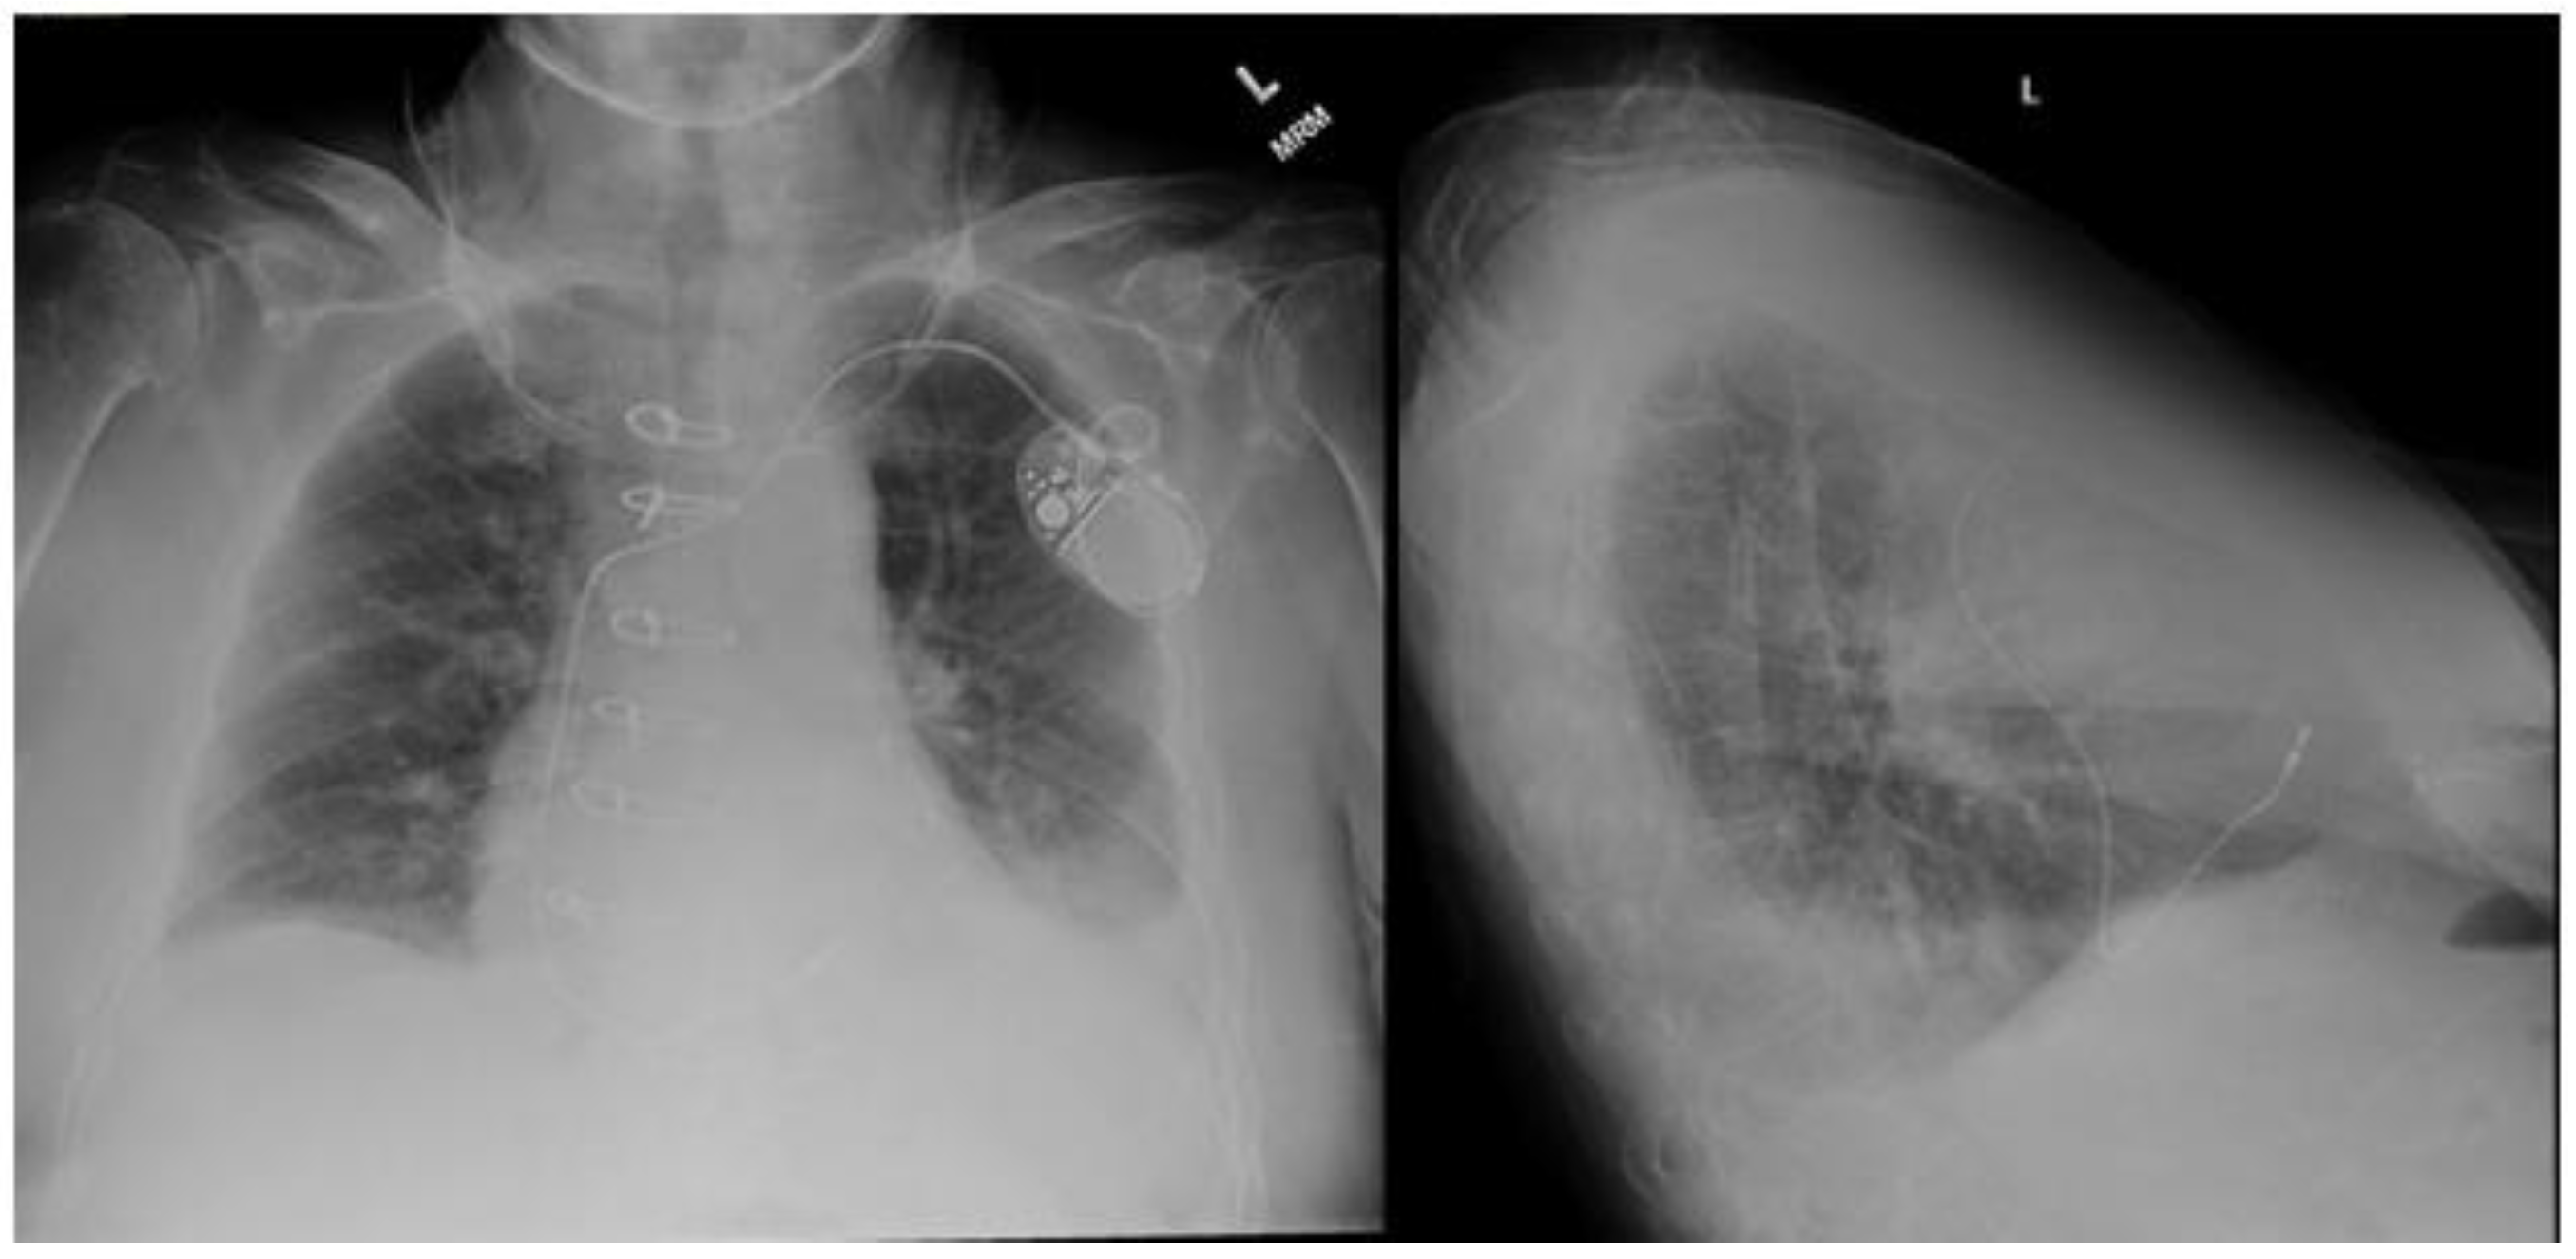

2.3.1. Chest Radiography